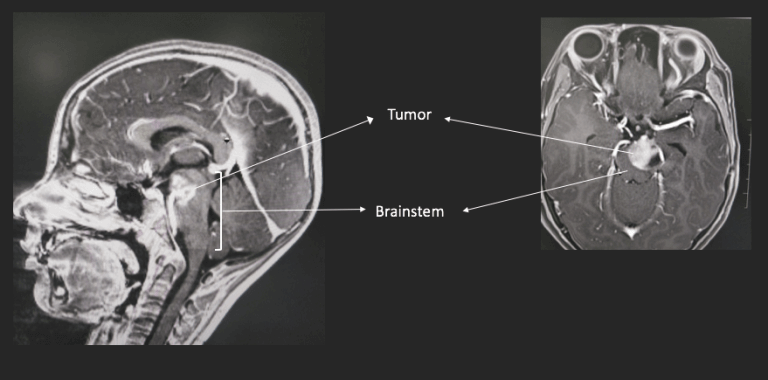

The brainstem glioma was discovered when the child complained of double vision and his parents noted an asymmetry in the child’s eye movements. And an MRI was done, which showed a tumor, roughly the size of a large marble, sitting in the brainstem on the left side. The tumor looked like a grade 1 tumor. This meant that while it would grow, it would grow slowly. And more importantly removing the glioma in it’s entirety could potentially mean cure. Cure is a rare word when it comes to brain tumors. Most often we look at control of growth, debate about progression free survival and dread the median time to recurrence.

The first step was more detailed imaging. We needed to know more about what was around the brainstem glioma – arteries, nerve bundles, anything that we had to ensure stayed undisturbed during surgery.

A second set of scans were thus done using a more powerful MRI machine (MRIs are basically large magnets and their strength is measured in Tesla, which is the unit of magnetic field strength. This one is the current strongest commercial machine, the 3 Tesla MRI). This gave us spectacular images of the anatomy of the lesion and also 2 very important bits of information. One, was that the basilar artery, which is a critical blood vessel was not engulfed and trapped in the glioma. The second involved a special MRI technique called diffusion tensor imaging (DTI). The technique actually allows us to see the nerve bundles in the brainstem as a colour coded map. In this case we found that there was a possible corridor of approach to the tumor which did not have any nerve bundles and was thus a safe entry zone.